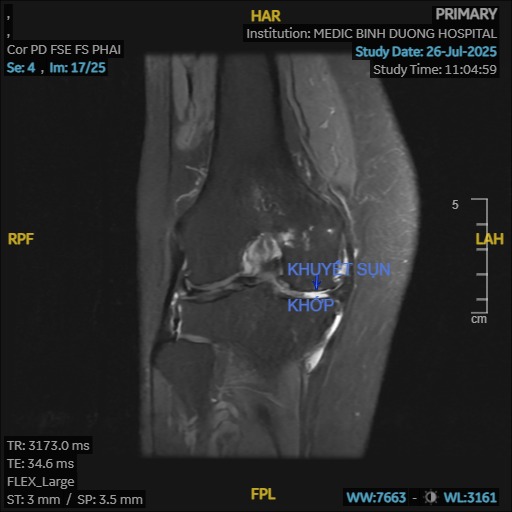

- Chấn thương: Các chấn thương cũ ở khớp gối (gãy xương, rách sụn chêm, tổn thương dây chằng) có thể làm thay đổi cấu trúc khớp và đẩy nhanh quá trình thoái hóa.

- Khớp phát ra tiếng kêu: Khi cử động khớp gối có thể nghe thấy tiếng lục khục, lạo xạo do bề mặt sụn khớp bị gồ ghề.

- Nội soi khớp: Cắt lọc, bào, rửa khớp, khoan kích thích tạo xương (microfracture), cấy ghép tế bào sụn.